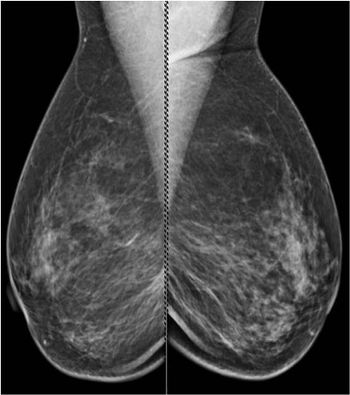

50-year-old patient presented for screening mammogram. Extremely dense breast tissue was noted.